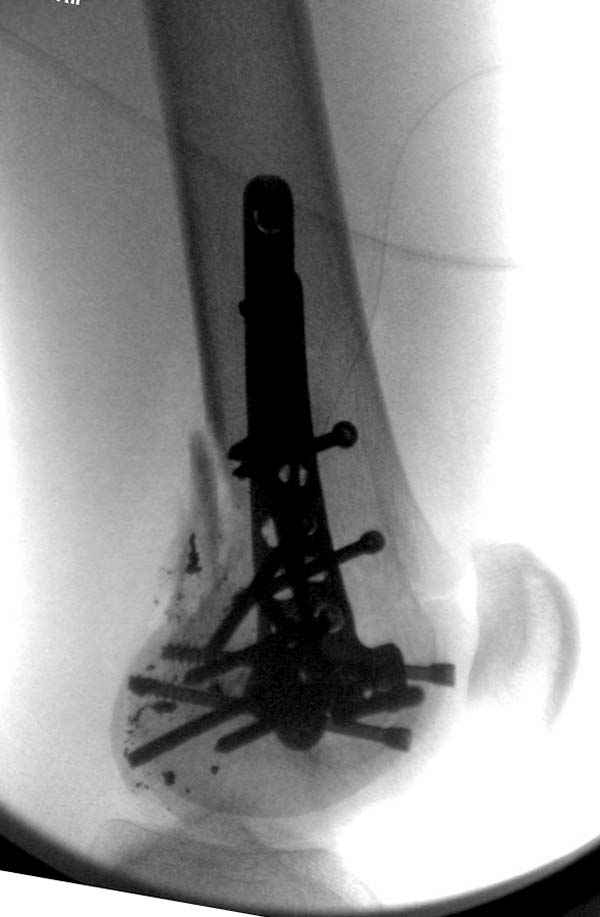

По Густило и Андерсену все high-energy переломы являются III не зависимо от степени повреждения мягких тканей. Plating такого перелома на второй день кажется немного рискованным хотя "победителей не судят". Судя по КТ, медиальный мыщелок стабильный, насколько необходимо было его фиксировать?

Красиво и быстро?! - две пластины + 18 шурупов.

Идеальная репозиция?! -На снимочке A-P проeкции видна "зазубрина" по суставной поверхности, латеральный снимок - тоже не идеально.

Множество мелких FB в кости.